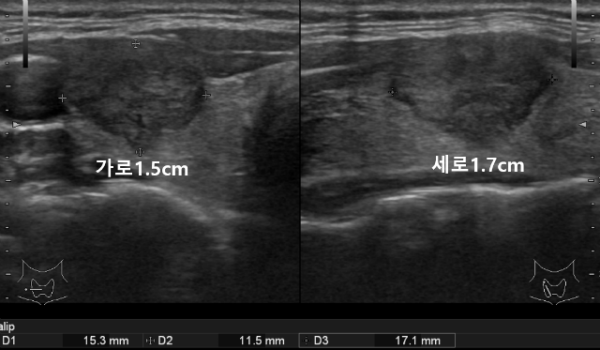

오른쪽 갑상선에 가로x세로의 길이가 약 1.5x1.7cm 크기의 불규칙한 모양과 경계를 보이는 저에코성 결절이 관찰되었으며 갑상선암이 의심되는 상황이었습니다.